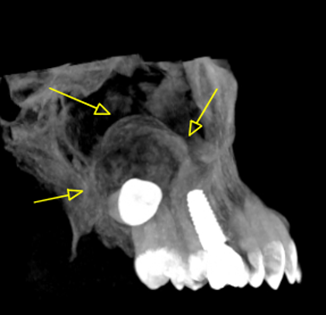

Περίπτωση ιδιαίτερα εκτεταμένης υπολειμματικής κύστης που καταλαμβάνει σχεδόν όλο το δεξιό ημιμόριο της άνω γνάθου εμπλέκοντας και το δεξιό ιγμόρειο άντρο σε γυναίκα ασθενή ηλικίας 75 ετών.

Η κύστη καταλαμβάνει πλήρως τη φατνιακή ακρολοφία στην οπίσθια δεξιά περιοχή της γνάθου και έχει προκαλέσει ιδιαίτερα εκτεταμένη υπέγερση του εδάφους του ιγμορείου άντρου προβάλλοντας εντός αυτού και καταλαμβάνοντας μεγάλο τμήμα της αεροφόρου του κοιλότητας.

Παρατηρείται επίσης ιδιαίτερα εκτεταμένη έκπτυξη και λέπτυνση του πλαγίου τοιχώματος του ιγμορείου άντρου, καθώς και των συμπαγών πετάλων της φατνιακής ακρολοφίας.

Σε αυτές τις περιπτώσεις η Υπολογιστική Τομογραφία Κωνικής Δέσμης (CBCT) μπορεί να βοηθήσει καταλυτικά στη διαφοροδιάγνωση αυτών των βλαβών αλλά και να αποκαλύψει με λεπτομέρεια την έκταση και τα όρια της βλάβης.